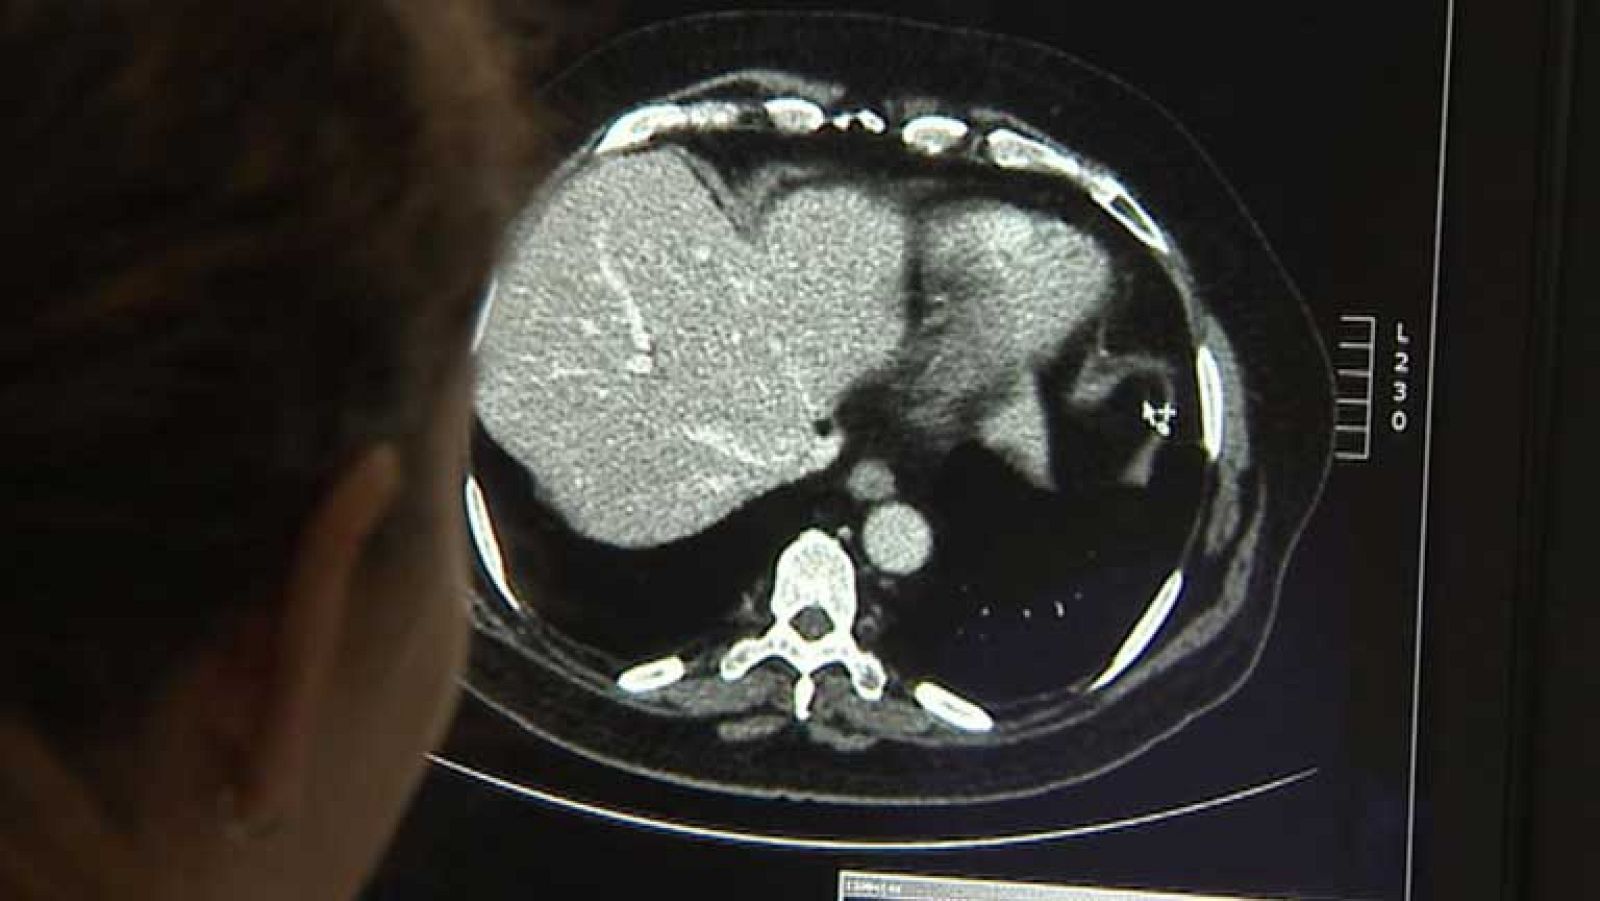

Día internacional de la radiología

Día internacional de la radiología